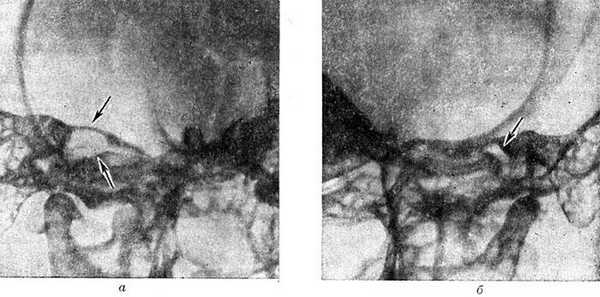

Рис. 4. Рентгенограммы по Стенверсу височных костей больного с невриномой правого слухового (преддверно-улиткового) нерва: а — виден резко расширенный правый внутренний слуховой проход (указан стрелками); б — нормальная ширина слухового прохода (указан стрелкой) левой (здоровой) височной кости.

Для большей достоверности рентгенол. признаков опухоли производят следующие парные краниограммы больной и здоровой сторон на одной пленке при идентичных условиях съемки: поперечные рентгенограммы височных костей по Стенверсу; прямые рентгенограммы с проекцией пирамид в глазницы; задние полуаксиальные рентгенограммы для выявления деструкции задней поверхности пирамиды. Основное значение имеют снимки по Стенверсу, дающие представление о размерах внутреннего слухового прохода на стороне опухоли, состоянии его верхней и нижней стенок, глубокой ампулярной части, об отношении опухолевого дефекта кости к капсуле улитки и вертикальному полукружному каналу лабиринта (рис. 4, я, б). Иногда более информативны снимки с проекцией пирамид в глазницы.

Рис. 5. Рентгенограмма по Стенверсу черепа больного менингиомой мостомозжечкового угла: стрелками указана тень обызвествленной опухоли.

По данным краниографии иногда можно дифференцировать различные опухоли М. у. Так, менингиомы редко вызывают расширение внутреннего слухового прохода, чаще деструкцию вершины пирамиды и ее поверхностей с неровными очертаниями, нередко наблюдаются известковые включения по периферии опухоли (рис. 5); при холестеатомах наблюдается резкое расширение внутреннего слухового прохода с разрушением передней поверхности пирамиды и линейные дугообразные известковые отметки с гладкими очертаниями узур прилежащих костей.

На вертебральных ангиограммах при невриномах слухового нерва сосудистая сеть опухоли контрастируется редко, в связи с чем главное значение имеют симптомы смещения сосудов (вторичные признаки). При каудальном распространении опухоли наблюдается прижатие базилярной артерии к скату (блюменбахову скату) и боковое смещение ее в противоположную сторону. При росте опухоли в оральном направлении базилярная артерия смещается кзади от ската и в противоположную сторону.

Верхнезадние мозжечковые артерии на стороне опухоли смещаются кверху и медиально. Нижняя мозжечковая артерия на стороне опухоли обычно смещается книзу. При менингиомах нередко видна сосудистая сеть опухоли.